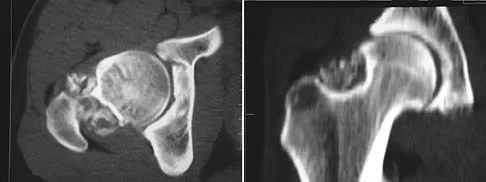

A 35-year-old patient has right hip pain. Figures 34a and 34b show the coronal MRI scan and the biopsy specimen. What is the most likely diagnosis?

Explanation

Alcohol abuse, steroids, Caisson disease, sickle cell disease, and radiation therapy are the leading causes of nontraumatic osteonecrosis of the femoral head. Arlet J: Nontraumatic avascular necrosis of the femoral head: Past, present, and future. Clin Orthop 1992;277:12-21.